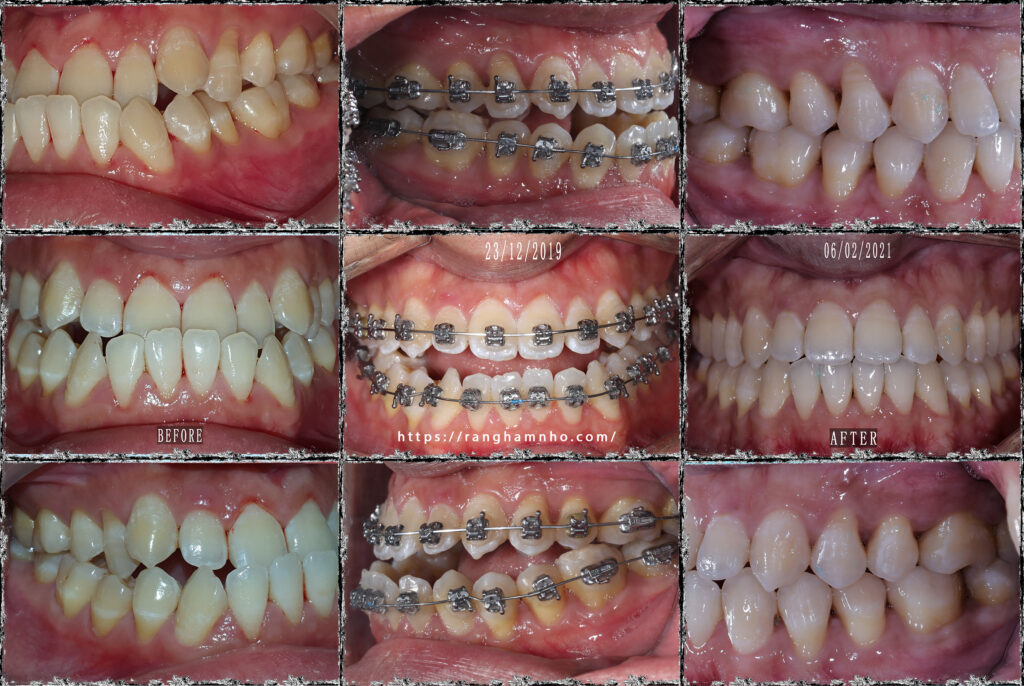

Bệnh nhân nam sinh năm 1993. Bệnh nhân đến với tình trạng khớp cắn ngược, hàm dưới phủ ngoài hàm trên, mặt lưỡi cày và các răng hàm dưới chen chúc nhiều. Răng hàm khớp cắn đối múi nhiều, không có sự lồng khớp tốt giữa hai hàm

Kĩ dây cung thẳng đa loop (kĩ thuật MEAW) được sử dụng để giải quyết tình trạng khớp cắn ngược. MEAW là một kĩ thuật điều trị bù trừ điều trị rất hiệu quả cho các trường hợp khớp cắn hạng III này, bệnh nhân không phải nhổ răng mà vẫn đạt được kết quả rất tốt.

Kết quả: giải cắn ngược, lồng múi hai hàm tuyệt đối, không còn răng đối múi. Mặt ngoài và nụ cười thay đổi ngoạn mục

Thời gian điều trị: 1.5 năm